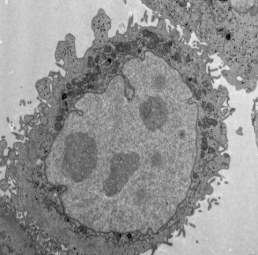

"小鼠肝脏透射电镜(制样+切片+拍摄)"商品可能已被商家删除,您可查看其他相似商品!